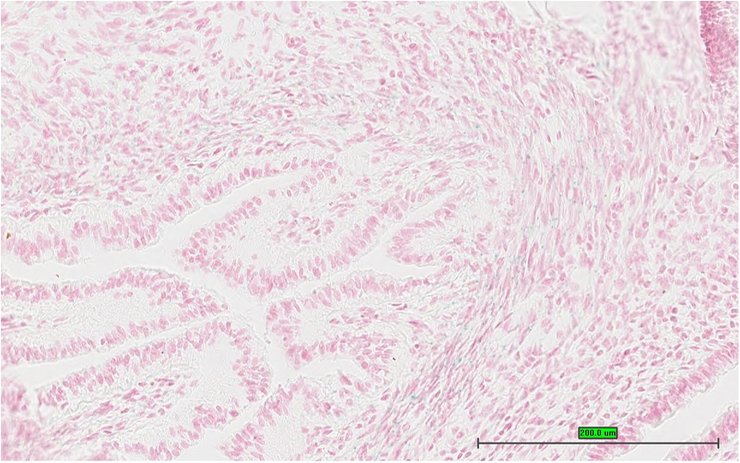

TS28: stomach Present UC Davis_1855958

Specimen UC Davis_1855959: postnatal adult; Mcamtm1.1(KOMP)Wtsi/Mcam+ (more )

Structure Level Pattern Image Note

TS28: stomach Present UC Davis_1855959

Specimen UC Davis_1855960: postnatal adult; Mcamtm1.1(KOMP)Wtsi/Mcam+ (more )

TS28: stomach Present UC Davis_1855960

TS28: stomach Present UC Davis_1856002

Specimen UC Davis_1856003: postnatal adult; Mcamtm1.1(KOMP)Wtsi/Mcam+ (more )

TS28: stomach Present UC Davis_1856003

TS28: stomach Present UC Davis_1856059